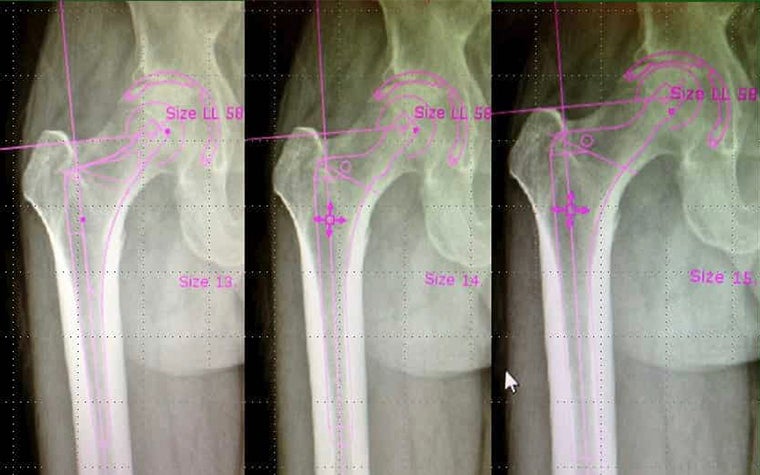

Surgeons can very easily template each surgery using the smart planning tools in OrthoView. “Templating with OrthoView is very fast and versatile, and the number of templates available to the surgeon is near limitless,” says Dr. Levine. In addition, the ability to access plans from any device at any time, even in the OR during surgery, is a huge benefit.

Plus, OrthoView helps with team collaboration, with surgical technicians able to review the digital plan and see the components and sizes that Dr. Levine already templated prior to surgery. This helps the technician prepare the back table with the appropriate instruments, helping the entire case to flow more efficiently.